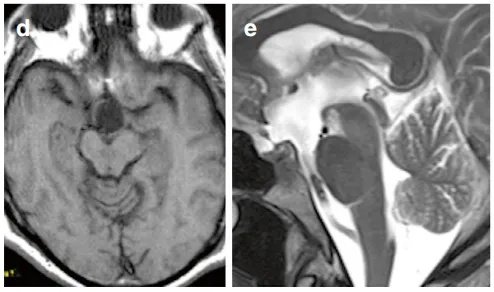

术后MRI证实肿瘤已肉眼全切(图d、e)。

手术未出现并发症,术后亦未见新发神经功能、认知或内分泌障碍。术后的局部美容效果良好,术后12天照片所示手术瘢痕已较为满意(图f)。